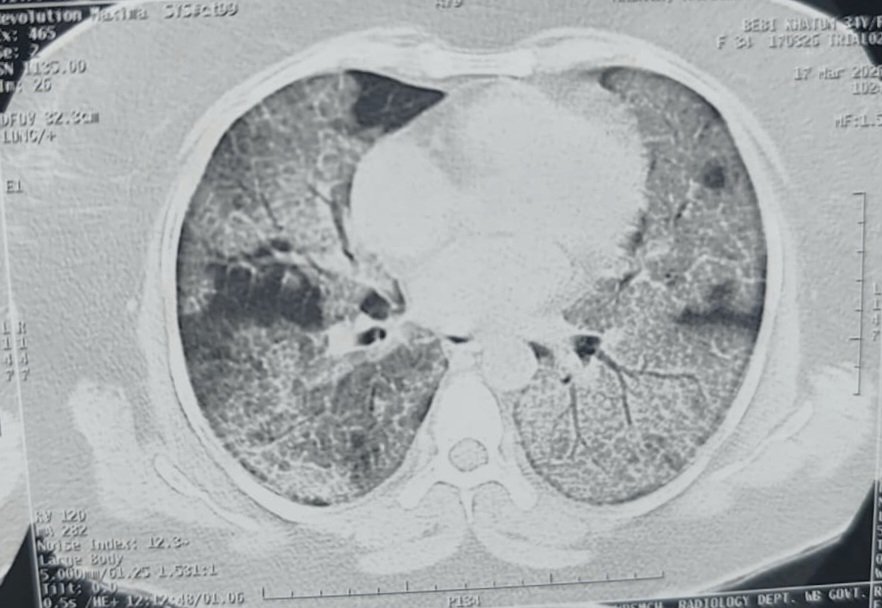

Ok this figure is pretty intimidating...